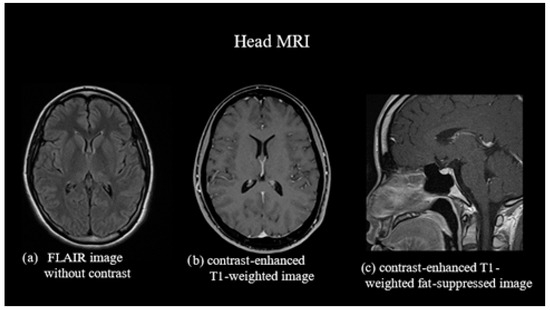

Non-contrast- and contrast-enhanced MRI of the head showed no dural edema. Contrast-enhanced T1-weighted images revealed no diffuse dural thickening or dilation of the epidural venous plexus (Figure 1). However, 111In cerebroventricular and spinal fluid space scintigraphy showed early cystic accumulation at 1 h (Figure 2), although spinal fluid leakage was not evident. Accumulation was also observed after approximately 6 h, and the residual CSF cavity radioisotope (RI) after 24 h was 15% (Figure 3), lower than the normal value of >30%.

Figure 1.

Magnetic resonance imaging (MRI) of the head. (a) Non-contrast fluid-attenuated inversion recovery image showing no subdural fluid accumulation. (b) Contrast-enhanced T1-weighted image showing no diffuse dural thickening. (c) Contrast-enhanced T1-weighted fat-suppressed image showing no dilation of the epidural venous plexus. FLAIR, fluid-attenuated inversion recovery.

Incidences of headache exacerbation in the supine position, as in the present case, have been reported as “paradoxical postural headaches” [7]. The mechanism believed to underlie this occurrence involves the dilatation of the cerebral venous sinuses and intracranial veins, which is aggravated in the supine position [7]. Subdural fluid accumulation, diffuse dural thickening, and dilation of the epidural venous plexus are characteristic findings of SIH on head MRI and are observed in 83, 61, and 75% of patients, respectively [8]. Although MRI results did not reveal any clear abnormalities, we speculated that the worsening headache in the supine position in this case was due to a compensatory increase in intracranial blood volume.